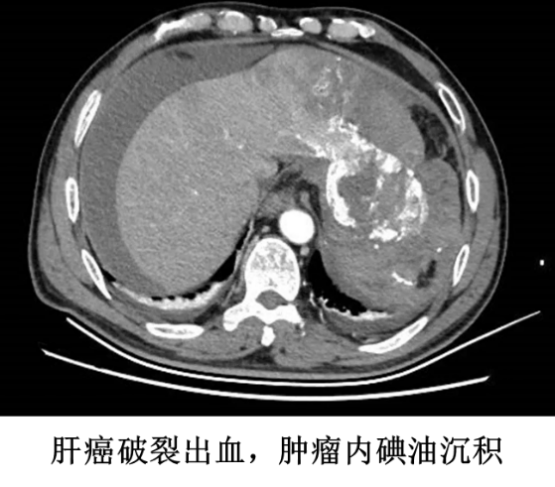

接到电话后,王恺立即安排科室同事做好接诊准备,并积极完善术前准备工作。根据患者家属描述,患者 2 天前突发腹痛,于当地医院行腹部 CT 检查提示肝癌破裂出血,并于当日在兄弟医院行急诊肝动脉栓塞术止血。术后第二天,患者诉腹部疼痛症状加重,复查血常规见血红蛋白仍呈下降趋势,血压下降、心率加快,提示仍有活动性出血并失血性休克。患者由急诊 120 转运至南昌大学第二附属医院急诊抢救室后,医院立即予以积极抗休克治疗,并迅速完成腹部增强 CT 检查,证实肝癌破裂出血并腹腔大量积血,估算出血量超过 2500 ml。

根据患者治疗病史、当前临床表现及影像学分析,患者的肿瘤位于左肝外叶,外生性生长,血供丰富,肝动脉栓塞后止血效果不佳。